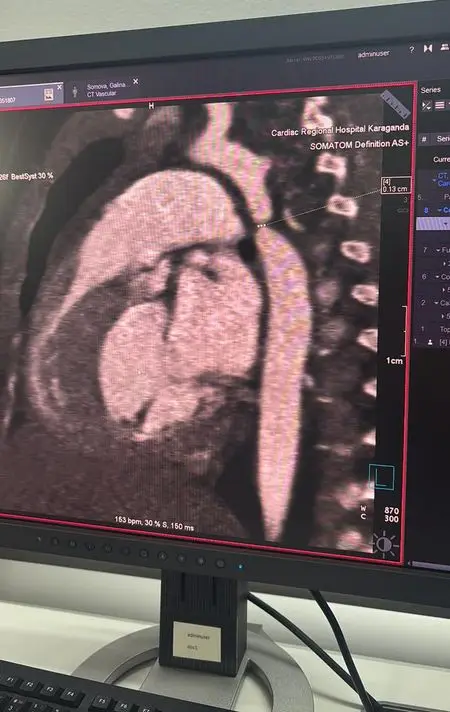

После выявления критической коарктации аорты, которая представляет собой врождённый порок сердца с резким сужением главного сосуда, девочку экстренно перевели в Кардиоцентр. Врачи провели консилиум и приняли решение о проведении операции в рамках мастер-класса с участием ведущих кардиохирургов страны. В Караганду прибыли кардиохирург Галымжан Утегенов и анестезиолог Хафиз Ахмеров из University Medical Center (UMC, Астана).

Операция длилась почти пять часов и включала резекцию коарктации аорты с наложением анастомоза "конец в конец", что позволило полностью восстановить кровоток. Во время вмешательства также была выявлена открытая артериальная протока, которую успешно легировали. Кардиохирург Галымжан Утегенов отметил, что операция была технически сложной, но прошла в плановом режиме.